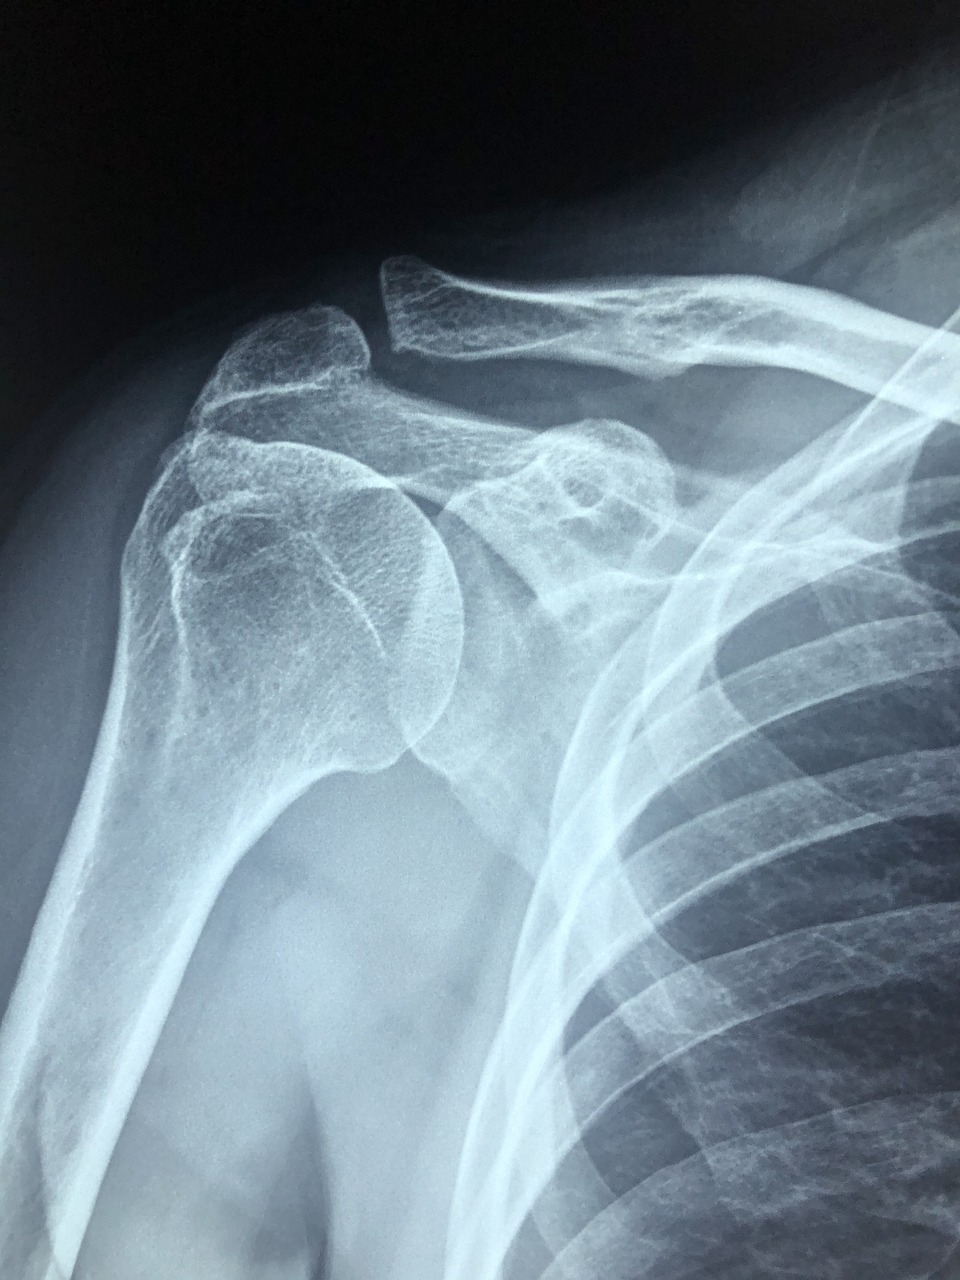

● 어깨석회화건염은 말 그대로 어깨 힘줄 속에 ‘석회질’이 침착되면서 염증을 일으키는 질환입니다.

● 주로 회전근개(어깨를 움직이는 힘줄)에 발생하며, 석회가 자라나면서 힘줄을 자극하고, 이로 인해 극심한 통증을 유발합니다.

● 조기 발견 시, 비수술적 치료로 충분히 좋아질 수 있으므로 통증이 있다면 빨리 병원에서 정확한 진단을 받는 것이 좋습니다.